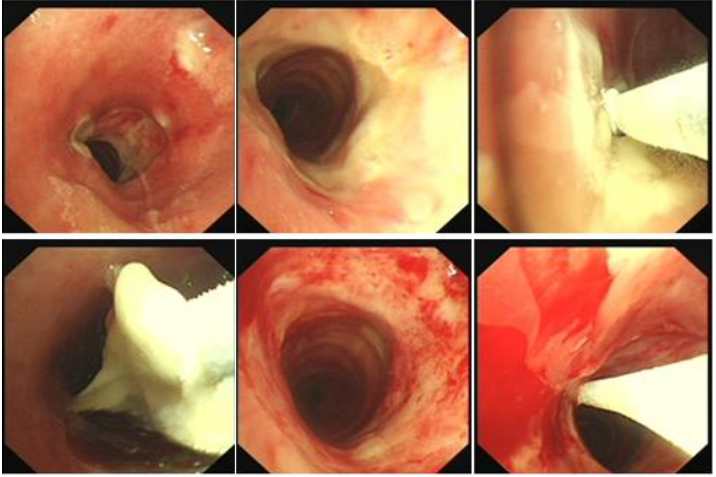

病例2:33岁,男性,全身多处淋巴结肿大1年,气促12天入院(2024年2月22日)。术前(2月22日):被动体位(前倾坐位,不能平卧),HR 136次/min,R 36次/min,SpO2 90%(FiO2 60%)。术前影像学如图24所示。紧急行气管镜检查:气管下段重度外压性狭窄,仅见缝隙,不能窥见隆突,软镜直视下置入金属覆膜支架(MTN-18/50)(图25),支架远端近隆突,术后气促明显改善。术后第4天(2月26日)咽部异物感明显,气促加重,复查胸片支架移位。再次行气管镜示:声门下腔见金属支架,经口取出支架,置入部分覆膜支架(18/40)(图26),支架远端近隆突,术后气促明显改善。B超引导下肿大淋巴结多点穿刺提示为弥漫大B淋巴瘤,后续行淋巴瘤相关治疗。病例3:64岁,女性,咳嗽、咯血、气促1个月入院(2021年12月11日)。气促明显但能平卧,HR 91次/min,R 24次/min,SpO2 94%(吸氧4 L/min)诊断未明确。外院转入。支气管镜检查:左、右主支气管内见新生物,左主混合性闭塞;右主狭窄,右中间段开口见缝隙(图27)。无外科手术指征,采取介入治疗。软镜局麻静脉镇静镇痛(咪唑安定+舒芬太尼),高频通气备用,术前使用甲基强的松龙40 mg静推,治疗策略为分步走,先处理左主,保证氧合:①左主置入导丝以备紧急情况下能快速置入支架;采用生理盐水加压注射法,支气管镜强行进入置入导丝;②充分冲洗清理左肺大量黏稠血性分泌物,防止分泌物溢出导致窒息。处理后患者氧合改善。再处理右主:①探查右中间段(缝隙),生理盐水加压注射法,支气管镜进入右中间段支气管,充分冲洗治疗;②右主支气管冻切活检(少量出血)明确诊断。下一步处理:首选Y型覆膜支架或双侧支气管支架置入,因患者诊断未明确、经济原因及考虑肿瘤的后续有效治疗,放弃Y型支架;左主混合性狭窄,仅在左主置入金属裸支架,右主新生物内镜下切除(冻切+APC)(图28)。2天后复查支气管镜, 左主支架膨胀良好, 右主及右中间支气管予以冷冻冻切残余新生物及消融后焦痂, 治疗后管腔较前进一步通畅(图29)。病例4:52岁,男性,重度呼吸困难,急诊2021年12月20日入院。气管镜检查:隆突浸润明显增宽(鳞癌),左/右主支气管重度外压性狭窄,左侧更明显(仅见缝隙)。第一步,先探查狭窄最重的左主,生理盐水加压注射进入左主,仅左主起始部重度狭窄,清理分泌物,同时置入导丝备用。第二步,探查右主,右上叶支气管基本正常,右主重度外压狭窄并右中间段开口呈缝隙,在生理盐水加压注射下支气管进入右中间段(仅右中间段起始部重度狭窄),冲洗出大量血性黏稠分泌物,置入导丝(图30)。首选Y型金属支架置入,如果没有Y型支架或缺乏置入Y型支架的技术能力,可以分别在左、右置入直筒支架。第三步:置入Y型覆膜支架(图31),使用刘志光改良的Y型支架置入装置(专利),软镜置入快捷(耗时10 min)。支架规格:18/40-14/30-14/20(右)。置入后,支架膨胀良好,呼吸困难显著改善。